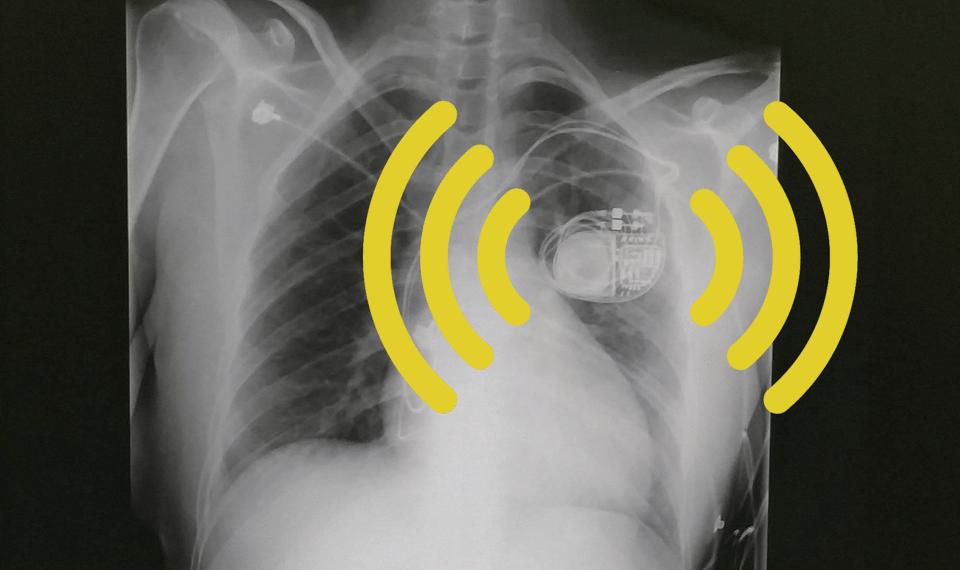

距离我34岁生日还有一个月,我就收到了一份意外的“礼物”:一个云连接的心脏起搏器。它位于我胸部左侧,就在我心脏的上方。这个装置可以说是温润如玉,勤劳苦干——它发出电脉冲,以确保我的心率不会再次骤降到每分钟25次以下。

这或许可以解释为什么我的心脏起搏器制造商——大型医疗设备公司美敦力(Medtronic),宣称该设备可以由医护人员或担忧患者状况的家庭成员对患者进行远程监控。可追踪性能可以有效缓解患者家属的焦虑,但同时也引发了些许对隐私和寿命的担忧。

尽管心脏起搏器在生活中的数量不断增加,更不用说像我身上安装的这种的最新式无线心血管设备,但它们的长期影响、风险和专利设计则很少被新患者或或者他们的家人论及。Lior Jankelson是纽约大学心脏-电生理学中心的医生,他告诉我,在美国,每一个植入的新起搏器都是与云连接的。“结果就是”,Jankelson解释说,“至少有成千上万的美国人拥有可以远程监控的云连接设备。”医疗机构可能会觉得,首先我们先来拯救你的生命,然后再说其他的比如这种无线设备、皮下植入装备的应用没准会把你的余生置于黑客、感染和其他健康危害之中这样的问题。

我的这台微型设备不断收集数据,每当我的医生安排远程监控预约时,这些数据就会自动发送到我床边的监视器里。这些预约每四到六个月进行一次,在此前间,监视器会将我的一些列指标发送给安全服务器。医生则在另一端检查传输的数据,并通过电话通知我是否需要采取进一步的行动。而患者手册是这么解释的:“使用无线技术发送心脏设备信息不需要您与监视器互动。这一过程是无声的,无形的。通常情况下,医院方面会在您睡觉的时候自动安排这一活动的进行。”